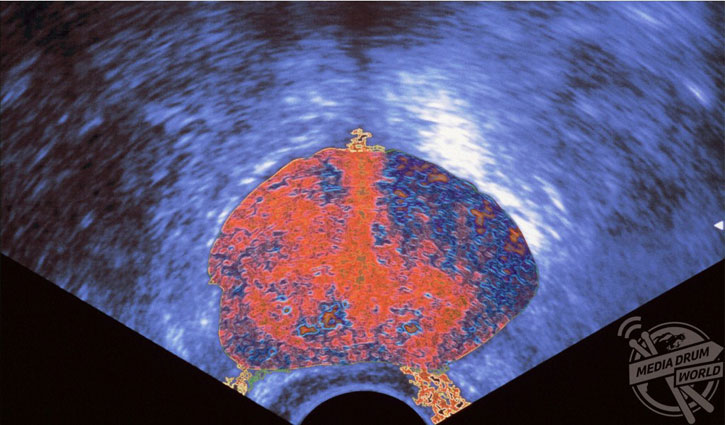

এই ছবিটি একজন মানুষের উদ্দীপ্ত প্রোস্টেট আল্ট্রাসাউন্ড স্ক্যানের। প্রস্টেট একটি ছোট গ্রন্থি, যা শুধু পুরুষদের থাকে। এটা মূত্রনালীকে ঘিরে থাকে এবং একটি পুরু অংশ ।